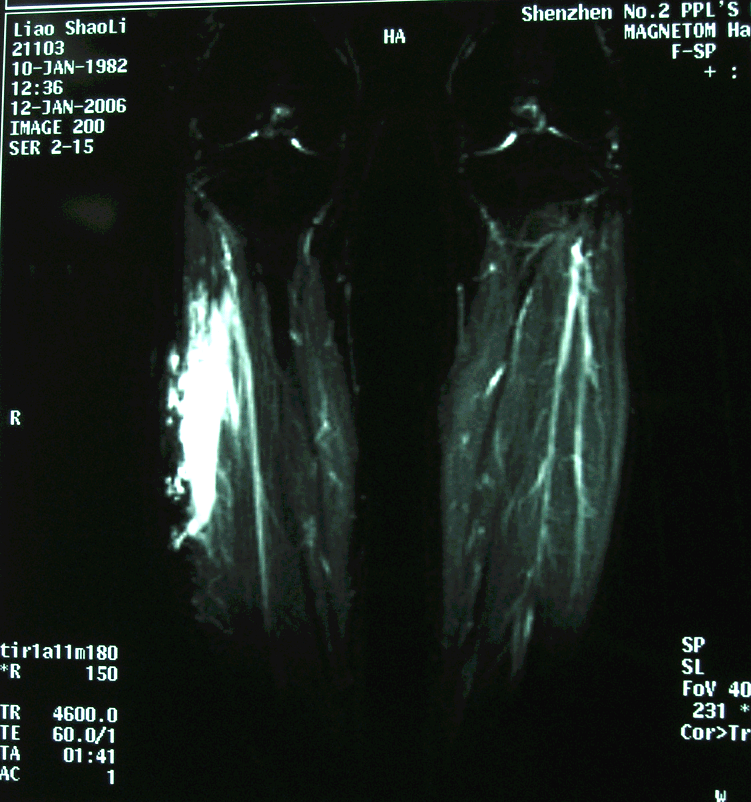

3.病例3:女 18岁,右下肢多发性深部肌内血管瘤,入院后行肿瘤扩大切除术。

右大腿MRI

右小腿MRI

右小腿病灶穿刺造影示扭曲扩张、粗细不均的血管